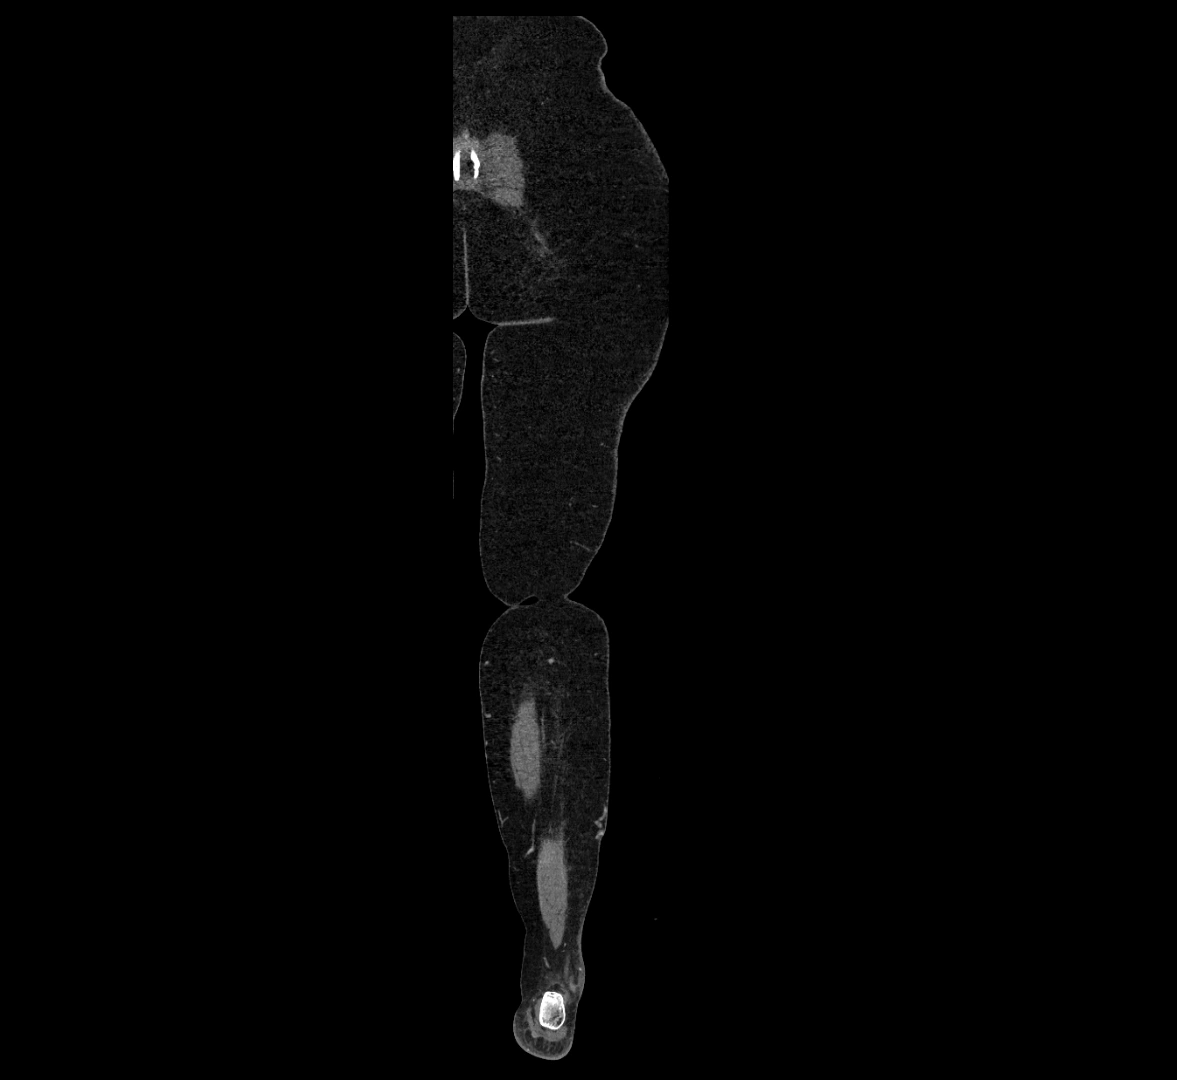

Contrast-enhanced CT (CTA):

• Gold standard for abdominal aortic imaging

• Provides excellent detail of lumen, wall, aneurysm, thrombus, and branch vessels

• Multiplanar and 3D reconstructions help in aneurysm measurement, stent graft planning, and dissection evaluation